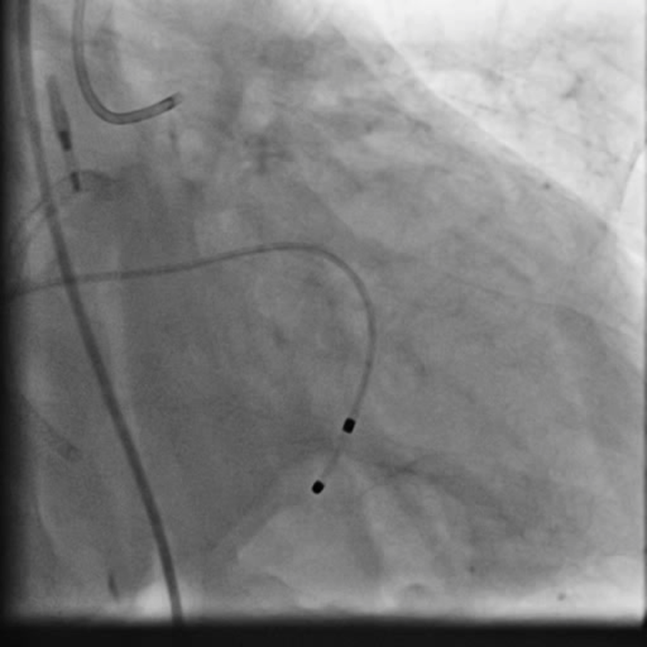

PCIof right coronary artery was initiated on IABP support with amplatz left1 guided catheter and vessel was crossed with great difficulty in repeatedattempts by fielder XT followed by GAIA 2 wire over corsair microcatheter. Microcathetercould not be crossed beyond mid segment calcified CTO, so balloon dilation with0.75 mm balloon was done after which again microcatheter could not be trackedbeyond mid part. Butwe were able to exchange wire to allstar followed by rotawire byplacing microcatheter in mid segment after balloon dilation by 0.75 mm balloon. Rotablation wasdone with 1.25 mm burr at 1,60,00 rpm repeatedly from proximal to mid distalpart. Lesionstill looked unprepared as repeated postdilation with2.25*15 mm followed by 2.5*15 mm non compliant balloon at high pressures showedunexpanded balloon. Againlesion preparation was done with 2.5*15 mm wolverine cutting balloon repeatedlyat high pressures which led to adequate luminal gain and calcium cracks as seenon IVUS run. AfterIVUS run again high pressure balloon dilation was done with wolverine 2.5*15 mmballoon followed by 2.5*12 mm non compliant balloon at 28 atm toadequately prepare the lesion before stent deployment. Stentingwas done with 2.5*32 mm DES, 2.75*32 mm DES, and 3*24 mm DES from distal toproximal in overlapping fashion. Thenfinally high pressure post dilation was done with 2.75*15 mm followed by 3*15mm non compliant balloon and adequate stent expansion was achieved with TIMI 3 flow.

Rightcoronary artery was well revascularized with adequate stent expansion and nosignificant complications. Patientwas weaned off from IABP support next day and regained his rhythm after 2 daysand then temporary pacemaker support was removed. Hewas planned for a staged rotablationguided PCI to left coronary system as he developed mild renal dysfunction whichgradually improved in hospital before discharge.